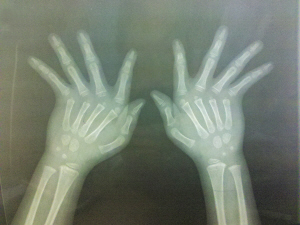

冬冬的手部。

冬冬(化名)今年5岁,来自河南。一岁开始抽条,小胖手变“瘦”下来后,父母发现,冬冬的双手有点奇怪,除了大拇指外,其他手指都往小拇指的方向倾斜。

越大,冬冬的手指歪斜越明显,将手指伸直时,中途会有停顿,听到“卡”一声才会被弹直。日常生活能自理,但担心上学后会被歧视,父母带着冬冬到武汉来求医。

协和医院手外科主任陈振兵说,检查结果表示,冬冬手指的肌肉、韧带、关节囊发育不良,导致关节松弛后倾斜,在医学上有个形象的名字,叫“风吹手样畸形”。虽不影响生活,但手指倾斜后,受力不均衡,可能磨损手指肌腱、韧带,或造成肌腱滑脱。